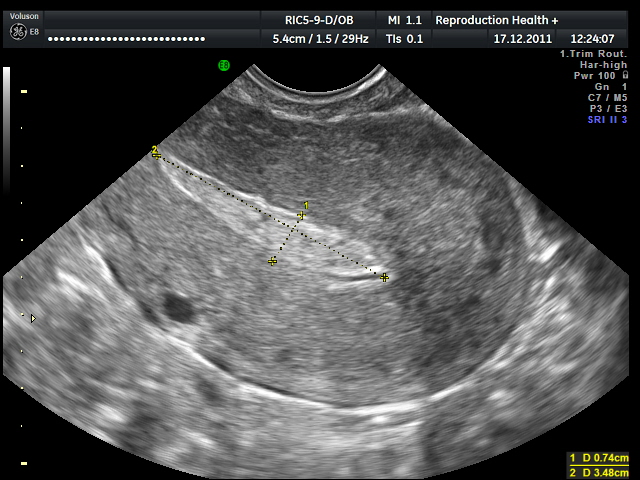

Матка после аборта на УЗИ

Основное, что видно на УЗИ в таком случае – это истонченный эндометрий. Но до определенного срока это является нормой. Можно на УЗИ также заметить и остатки продуктов гестации. То есть, иногда после аборта в полости матки остаются частицы плодного яйца, которые необходимо незамедлительно удалять, так как они могут стать причиной воспалительного процесса. Но остатки продуктов гестации обычно имеют место только при аборте на позднем сроке более 7 недель.

Гипоэхогенные включения на УЗИ могут быть признаком серьезных патологий. Они могут свидетельствовать о перфорации матки, говорить о скоплении в ней крови, остатках продуктов гестации, начинающемся эндометрите и т. д. Именно такой высокой информативностью УЗИ и объясняется то, что данная процедура почти всегда назначается после аборта.